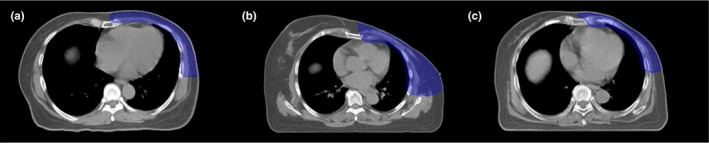

This study included 30 patients who were treated by helical tomotherapy at our institution for left‐sided PMRT between January 2017 and December 2018. The treatment targets were classified in three situations, with ten patients per each situation. Figure 1 illustrated the CT images and structure for the patients in the first situation received only chest wall (CW) treatment. The second situation was the patients with chest wall treatment that included supraclavicular lymph nodes (CW + SPC). The third situation treated the chest wall including supraclavicular and whole axillary lymph nodes irradiation (CW + SPC + AXLN). All patients underwent 3D simulation in the supine position on the wing board (CIVCO, USA) with both arms up above the head. Computed tomography (CT) as performed with a slice thickness of 3 mm. and using radiopaque wires to define the scars and field borders on the patients’ skin during CT simulation.

Fig. 1.

The coronal view of the computed tomography (CT) images and structure for the patients (a) the first situation (chest wall only), (b) the second situation (chest wall included supraclavicular lymph nodes), and (c) the third situation (chest wall included supraclavicular and axillary lymph nodes irradiation).

Regarding the heart dose, all treatment techniques could not pass the criteria for mean heart dose and V10Gy because the PTV CW showed a very thin shape and close to the heart volume as shown in Fig. 3. The higher mean contralateral lung dose for TD plans due to the wide PTV and the body shape of patients. Other reasons were the beam direction of TD plans, six tangential direction, and another beam in anterior oblique direction may cause of increasing the low dose for contralateral lung.

Fig. 3.

The transverse view of the computed tomography images of planning target volume chest wall structure (blue color) for one patient for each situation (a) the first situation (chest wall only), (b) the second situation (chest wall included supraclavicular lymph nodes), and (c) the third situation (chest wall included supraclavicular and axillary lymph nodes irradiation).